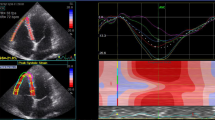

Measurement of right ventricular strain

Strain measurements by two-dimensional speckle-tracking echocardiography method were conducted according to the recommendations of the current echocardiography guideline [16]. All of the images were analysed using 2D AutoStrain software (Qlab, Philips Healthcare, Andover, Massachusetts). Since there was no software to process the right ventricular strain pattern, the software for the left ventricular strain pattern was used. After tracing the RV endocardial border, the region of interest was automatically generated. Global right ventricular free wall strain value was calculated as the mean of the strain values in the 3 segments of the RV free wall.

Echocardiography parameters were given in the Table 2. LVEDD and LVESD, IVS and PW, LVEF and LA diameters were similar between the groups. By using PW, while late diastolic peak velocity (A) was higher in the patient group compared to the healthy group, transmitral early diastolic peak velocity (E) was similar in both groups. While the RV height was significantly higher than the control group, the right ventricular end-diastolic diameter was lower than the control group. Right ventricular end-diastolic and end-systolic area were statistically higher than control group (p < 0.001). The RVFAC was significantly less in the patient group compared to the control group (43.4 ± 7.8 vs. 51.5 ± 6.2; p < 0.001). TAPSE was within normal limits in both groups however, it was lower in the patient group compared to the control group (p 0.006). Pulmonary artery pressure was found to be significantly higher in the patient group compared to the control group (27.9 ± 4.8 mmHg vs 22.2 ± 7.3 mmHg; p < 0.001). While PW and transtricuspid early diastolic (E) were similar in both groups, late diastolic (A) was lesser in control group.Tricuspid valve S, E, A values evaluated by tissue Doppler were similar in both groups. MPI calculated by right ventricular tissue Doppler was significantly higher in the patient group compared to the control group (0.58 ± 0.06 vs. 0.39 ± 0.04; p < 0.001). Right ventricular GLS was measured less than the control group (− 15.7 [(− 12.6)–(− 18.7)] vs. − 18.1 [(− 14.8)–(− 21)]; p 0.011). Right ventricular free wall strain was found to be significantly less in the patient group compared to the control group (− 16 [(− 12.7)–(− 19)] vs − 21.6 [(− 17)–(− 25.3)]; p < 0.001) (Fig. 1).